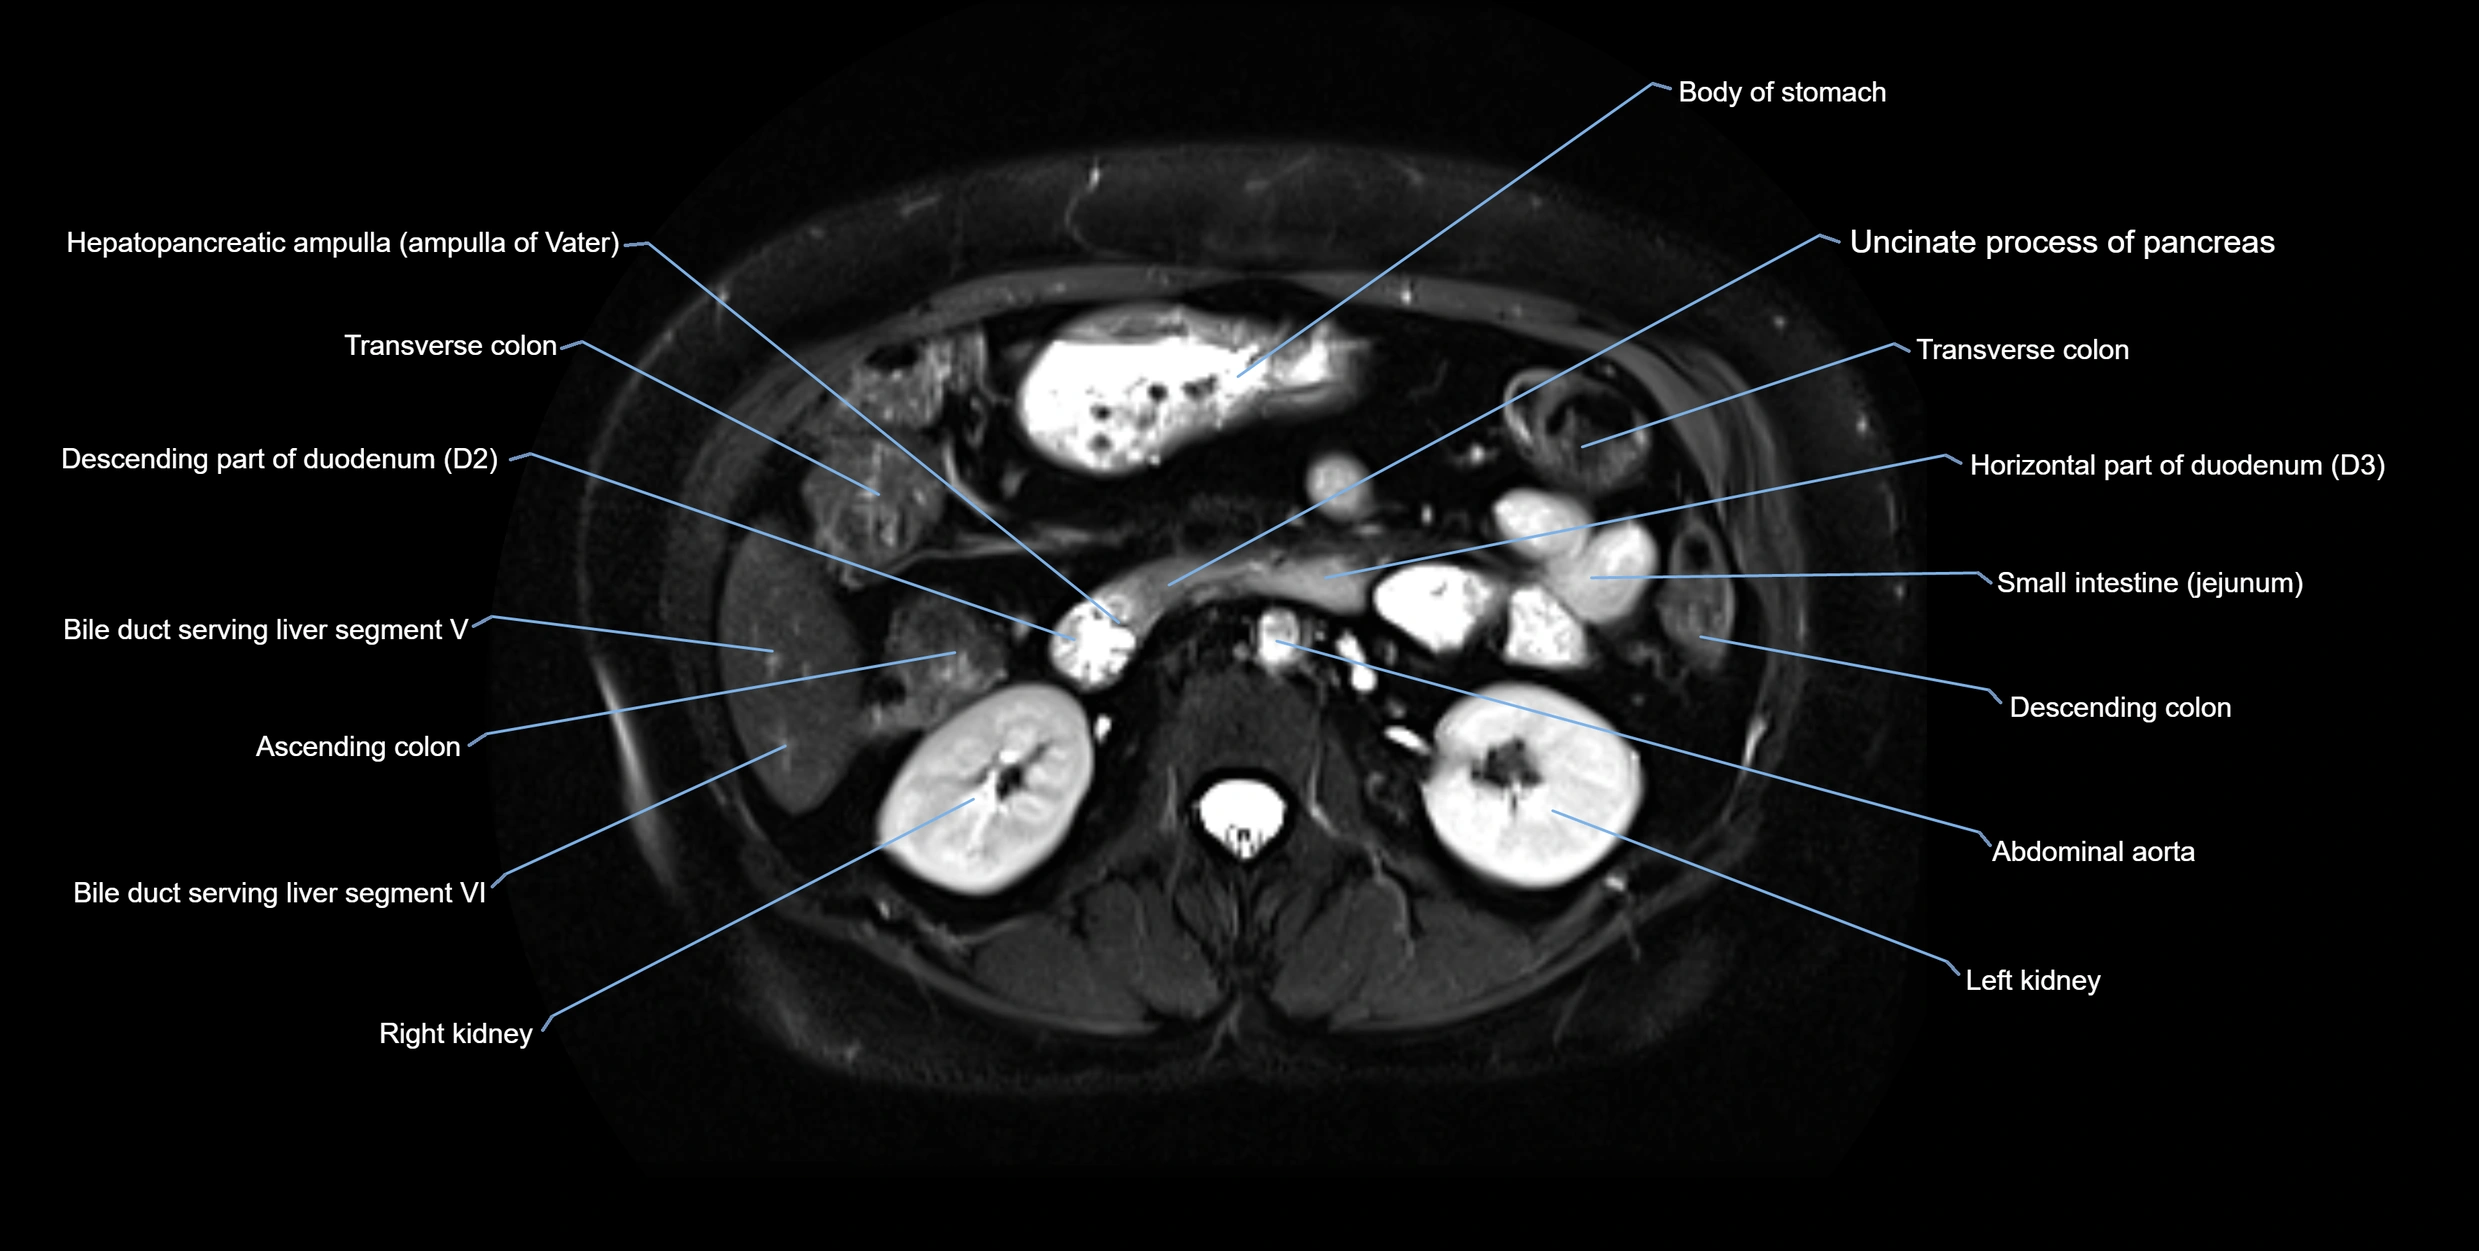

T2 TSE Fat-Saturated 3D (MRCP sequence):

• Duct visualized as a continuous bright tubular structure joining or parallel to the main pancreatic duct

• Allows 3D reconstruction of ductal anatomy and variants

• Excellent for diagnosis of pancreas divisum

Thick-slab T2 Fat-Saturated HASTE:

• Shows the accessory duct as part of the biliary–pancreatic system in a projectional image

• Highlights communication with main pancreatic duct and opening into the minor papilla

• Filling defects (stones, strictures) seen as dark spots within bright fluid

MRI image

image